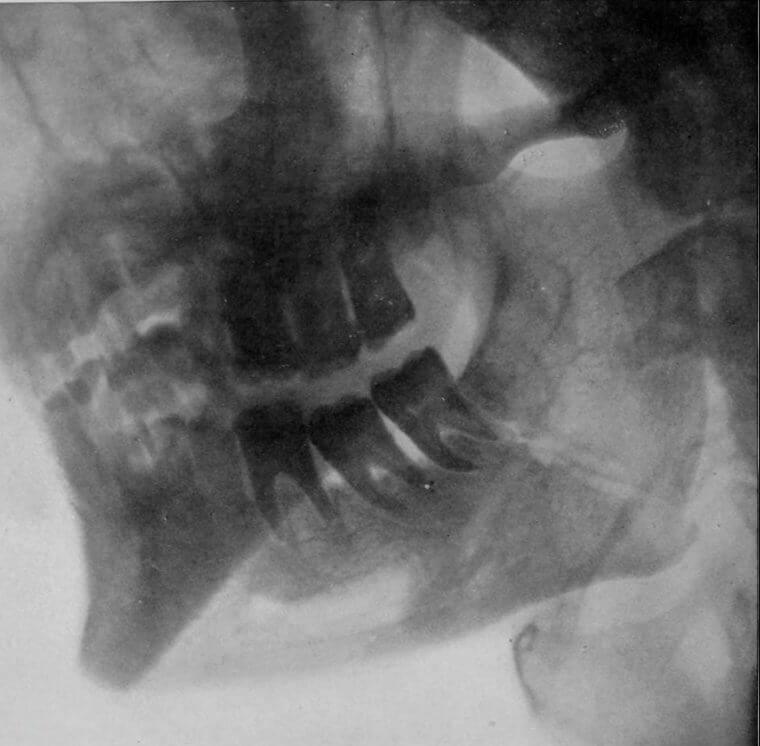

Teeth Don't Just Grow Inside Your Mouth

As John Mayer sang, 'Your body is a wonderland' and for women, it truly is, although this fact might not be considered wondrous by all. For some women, they are born with a dermoid cyst, which sounds like a normal cyst but it is not. These cysts are more like sacs and they can contain all sorts of goodies like hair, skin glands, and one more thing that should be found in a mouth.

That's right, these cysts can also have teeth growing inside of them. Can you imagine having a cyst with hair and teeth in your ovaries?

A Tumor Might Appear To Be Slightly Humanoid On Closer Inspection

The human body is a marvel. It can grow a baby, mend broken bones and so much more. Some people have tumors that grow in their bodies, and while some can be malignant and lead to cancer a lot tend to be benign. Certain tumors can confuse doctors because they tend to have some very human traits that you might find with a fetus for example. Do you know what these are?

Some tumors have hair and teeth that end up growing on them. Can you imagine a doctor's face when they notice one of those on an X-ray? It is like an episode of 'Grey's Anatomy.